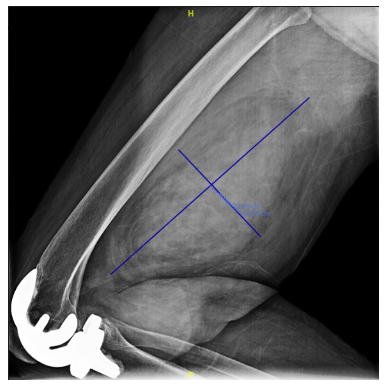

Primary leiomyosarcoma of bone is a rare type of malignant bone tumor. It most commonly occurs in the area behind the tissue that lines the abdomen (the retroperitoneum) and the pelvis. Leiomyosarcoma is also a malignant tumor than can occur in soft-tissue.